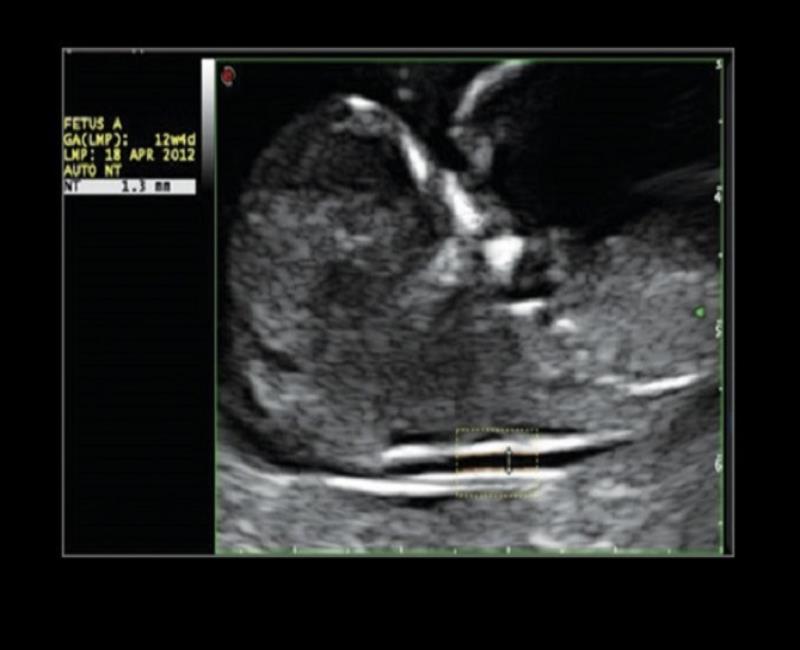

AutoNT – Tự động đo độ mờ da gáy. AutoIT – Tự động đo lớp trong mờ vùng gáy.